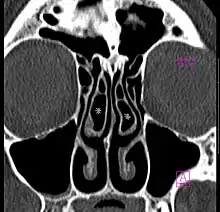

Concha bullosa

Concha bullosa on both sides (marked with asterisks), coronal orientated image from CT

A concha bullosa is a pneumatized (air-filled) cavity within a nasal concha, also known as a turbinate.[1]

Bullosa refers to the air-filled cavity within the turbinate.[1] It is a normal anatomic variant seen in up to half the population. Occasionally, a large concha bullosa may cause it to bulge sufficiently to obstruct the opening of an adjacent sinus, possibly leading to recurrent sinusitis[1] and various head pains related to areas innervated by the trigeminal nerve.[2] In such a case the turbinate can be reduced in size by endoscopic nasal surgery (turbinectomy). The presence of a concha bullosa is often associated with deviation of the nasal septum toward the opposite side of the nasal cavity.[3]